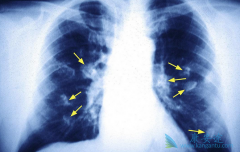

虽然现在已经是一种比较常见的癌症了,大部分的肺癌患者被查出来都是 肺癌晚期 了,晚期已经是很难治愈了的。其实在发现肺癌之前是有一些暗号表示自己已经有肺癌了的,这个时候人们就应该多关注自己的身体,看一下有哪些地方不对劲,如果及时发现是早期 ...

肺癌晚期都会出现哪些增加患者痛苦的症状,这些痛苦不仅包括身体上的,还有心理上的,包括焦虑,忧愁,恐惧等,采取措施给减轻患者病痛,给患者心理带来些许安慰,让患者好过一些也是治疗的重要部分。下面给大家介绍 肺癌晚期症状 。疼痛。肺癌引起的疼 ...